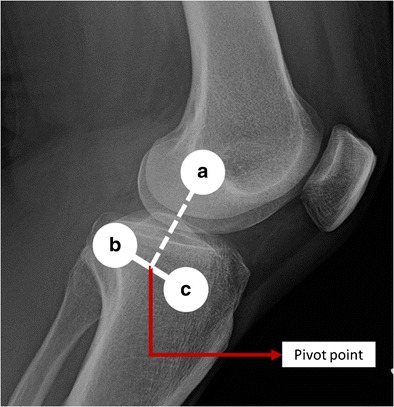

A good correlation between a–p translation of the lateral compartment and the results of the clinical pivot shift test grade as shown are the basis for image analysis software [17] (Fig. 2). This allowed for clinical marking of associated lateral compartment landmarks which could be captured with a high-resolution camera and processed accordingly. The bony landmarks of interest include the lateral epicondyle, Gerdy’s tubercle, and the fibular head. With a digital camera, the intersection between the connecting line of Gerdy’s tubercle and fibular head, and the perpendicular running connection to the lateral epicondyle is captured and deemed the “pivot point.” The ratio of the distances between the pivot point and Gerdy’s tubercle, and between Gerdy’s tubercle and fibular head is then used to calculate the femoral AP position from the Gerdy’s point. The anterior–posterior translation of the femoral AP position from the Gerdy’s tubercle dependent during the pivot shift over time illustrates a sudden decrease (Fig. 3), occurring simultaneously to the reduction of the tibia, in ACL-deficient knees. This sudden decrease is used for the quantification of the pivot shift. However, ACL-intact knees do not show such a decline of the femoral AP position. This highlights the biomechanical role of the native ACL in rotatory stability. Using electromagnetic tracking to digitize the actual bony movement, a correlation with the motion of the skin markers was confirmed, so that the principle of image analysis was shown to be valid. Using a novel tablet-based software, the analyzing time is approximately to 10–15 s, with an average error of less than 6 % in distances less than or equal to 175 cm between tablet computer and marker position. A user-friendly interface is implemented to simplify the clinical application. All alterations considered these adjustments make simple image analysis to an easily applicable tool for the daily clinical work [40, 41•].

Fig. 2.

Anatomic landmarks: a lateral femoral condyle, b fibular head, and c Gerdy’s tubercle. The intersection of the line between fibular head and Gerdy’s tubercle and the perpendicular connecting line to the femoral condyle is defined as the pivot point. By calculating the translation of the pivot point during examination, the lateral compartment translation can be quantified